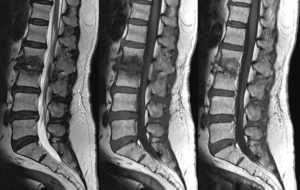

- Магнитно-резонансная томография. Является одним из самых достоверных способов исследования позвоночника. Благодаря наличию сильного электромагнитного поля на мониторе компьютера отображается структура дисков и их малейшие изменения. При патологии визуализируется обширный участок воспаления с поражением ближайших позвонков, а при дисците обнаруживается ограниченная патологическая область.

Магнитно-резонансная томография показывает даже незначительные изменения структуры межпозвоночных дисков